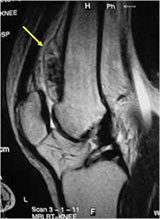

MRI:

- Mass on surface of bone

- Intermediate signal on T1 weighted images and high signal on T2 consistent with cartilage

- Usually no intramedullary invasion but may see slight erosion or saucerization of cortex

- Periosteal reaction evident on MRI as very low signal on T1 and T2 weighted images